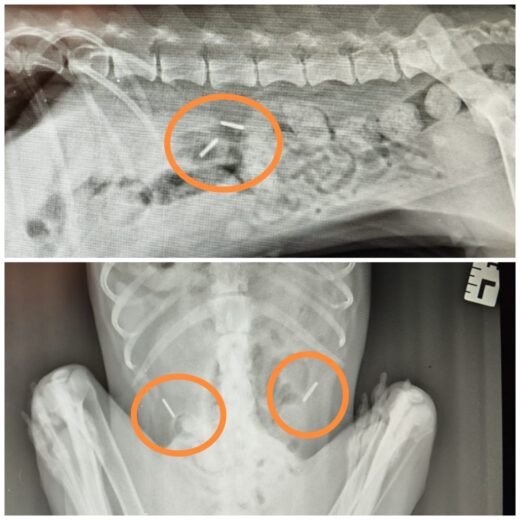

Ostatni moment na pomoc

Pani Żaneta zauważyła, że z jej przygarniętą kotką dzieje się coś bardzo złego – zwierzę zwijało się z bólu, nieczytaj więcej